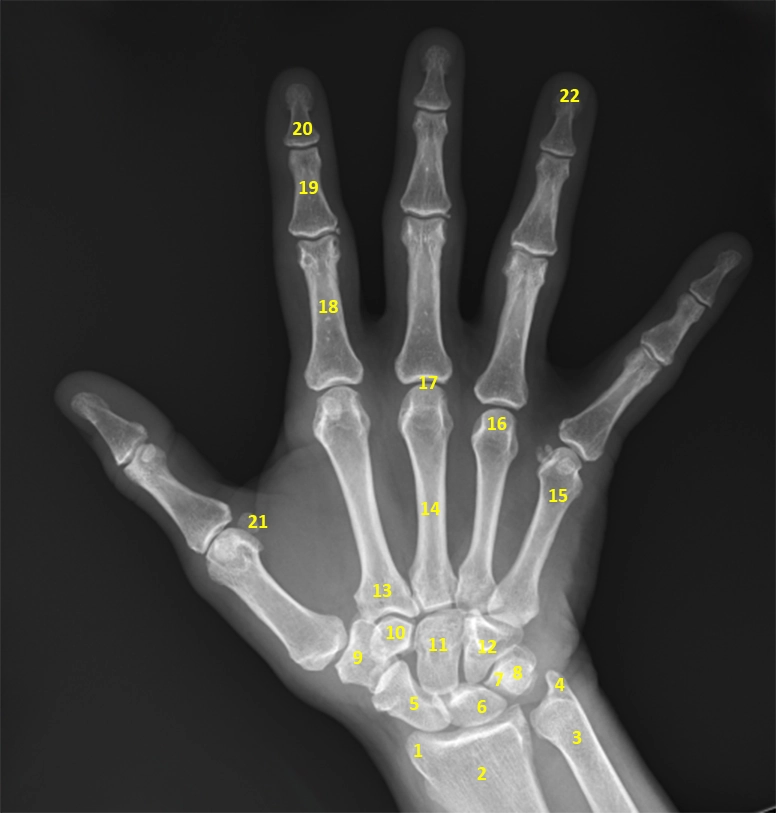

X Quang bàn tay